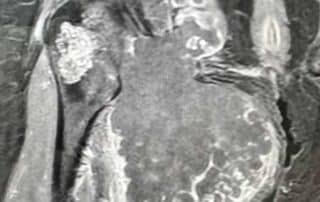

Dès 2006, il a démontré la possibilité de réaliser simultanément deux prothèses de hanche sur le même patient (références 23 à 28), stratégie qui est désormais utilisée par le Docteur Jean-Luc Raynier, et il a mis en évidence les limites des cupules de resurfaçage de hanche (référence 29). Il est également spécialiste de la reconstruction osseuse par Ingénierie tissulaire, sujet de sa thèse de science, objet de nombreuses publications internationales depuis 2005 (références 30 à 36). Enfin, le Professeur Trojani est spécialisé dans les interventions exceptionnelles en chirurgie tumorale, au niveau du genou et du bassin (Figures 3 à 5).

Figure 3 : chirurgie de résection complète du fémur avec mise en place d’une prothèse de fémur total, c’est-à-dire simultanément d’une prothèse de hanche et d’une prothèse de genou, du fait d’une tumeur osseuse atteignant tout le fémur (Sarcome d’Ewing).